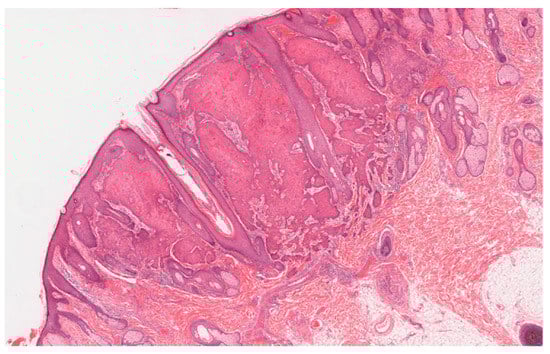

1. Clinical Features